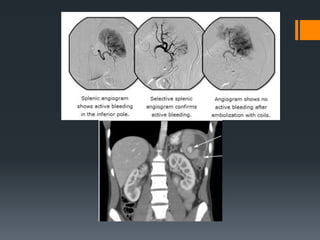

Splenic Trauma